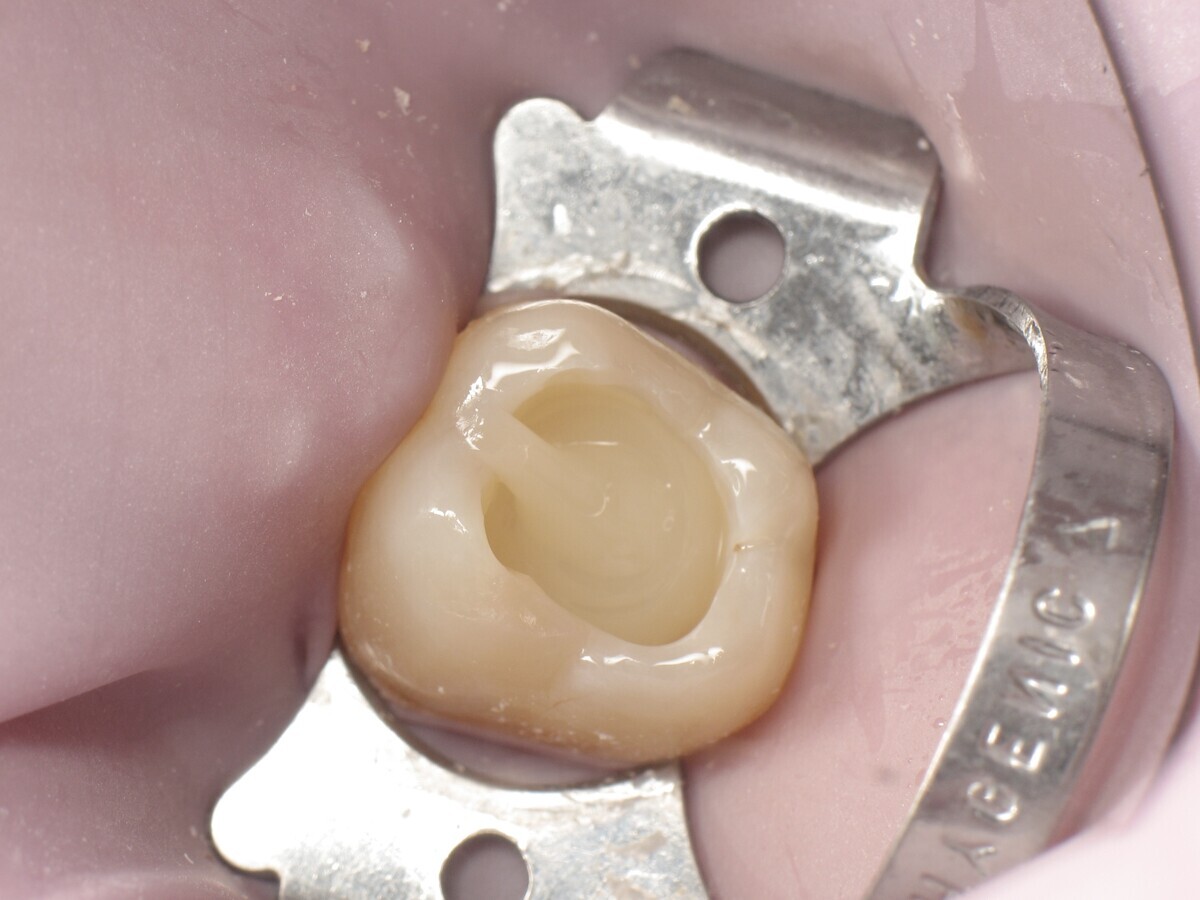

La secuencia fotográfica muestra la cavidad después de la aplicación y fotopolimerización del adhesivo y el modelado que se obtiene con el composite termoviscoso. Fotos: Yassine HARICHANE

Este artículo describe el tratamiento de una cavidad clase I en un molar utilizando un composite termoviscoso mediante la técnica de la almohadilla (Figura 1). En primer lugar, se registran los detalles anatómicos utilizando una resina transparente, fluida y fotopolimerizable (Clip Flow, VOCO). El diente se aísla con un dique antes de aplicar el composite transparente a la superficie oclusal con un cepillo aplicador y fotopolimerizar durante 10 segundos (Figuras 2-4). La almohadilla oclusal así obtenida (Figura 5) debe almacenarse en alcohol (etanol o isopropanol) para eliminar la capa de inhibición. Luego se limpia la cavidad clase I (Figuras 6 y 7). A continuación se graba el esmalte durante 30 segundos y la dentina durante 15 segundos (Conditioner 36, Dentsply Sirona) y luego se enjuaga bien (Figuras 8 a 10). Debido al bajo espesor de la dentina remanente, también se aplica protección pulpar (Telio Desensitizer, Ivoclar Vivadent) (Figura 11). Luego se frota el adhesivo sobre las superficies dentales durante 20 segundos (Futurabond DC, VOCO), luego se seca bajo una pulverización de aire sin aceite graso durante 5 segundos y luego se fotopolimeriza durante 10 segundos (Figuras 12, 13). Para una humectación óptima, el fondo de la cavidad se cubre con un compuesto fluido de baja viscosidad (GrandioSO Light Flow, A3.5, VOCO) y se fotopolimeriza durante 20 segundos (Figuras 14, 15). Utilizando el Dispensador VisCalor, un dispensador portátil que permite el calentamiento y la aplicación simultánea de resinas, la cavidad se llena luego con un composite termoviscoso bulk (VisCalor Bulk, A2, VOCO).

El composite calentado tiene una consistencia fluida para un perfecto manejo y se puede aplicar en capas de hasta 4 mm (Figura 16). A medida que se enfría hasta la temperatura corporal, la viscosidad del composite termoviscoso aumenta, lo que lo hace muy fácil de modelar (Figura 17). Finalmente, se realiza la fotopolimerización durante 20 segundos (potencia ≥ 1.000 mW/cm2, Figura 18). El uso de un composite bulk permite un llenado rápido en un solo paso. Si se requiere una segunda capa, la capa superior también se puede realizar con composite termoviscoso estético universal VisCalor en color A1 (VisCalor, VOCO, Figura 19), que se fotopolimeriza en incrementos de 2 mm. La consistencia innovadora del composite termoviscoso permite una reproducción fácil de la anatomía y una eliminación fácil del exceso de material (Figura 20) [Ilie et al. 2014]. A continuación se aplica la almohadilla oclusal creada previamente (Figura 21). La fotopolimerización se realiza primero con la almohadilla y luego sin durante 20 segundos cada una (Figuras 22 a 24). No se requiere material separador entre el material compuesto y la almohadilla. Debido a la eliminación previa de la capa de inhibición de la almohadilla, hay muy pocos o ningún punto de contacto, de modo que no se puede crear ningún enlace químico real entre la almohadilla y la resina. Los pocos puntos de contacto presentes solo significan que puede sentir una ligera resistencia cuando se retira la almohadilla después del primer ciclo de fotopolimerización.

Figura 21. Aplicación de la almohadilla oclusal.